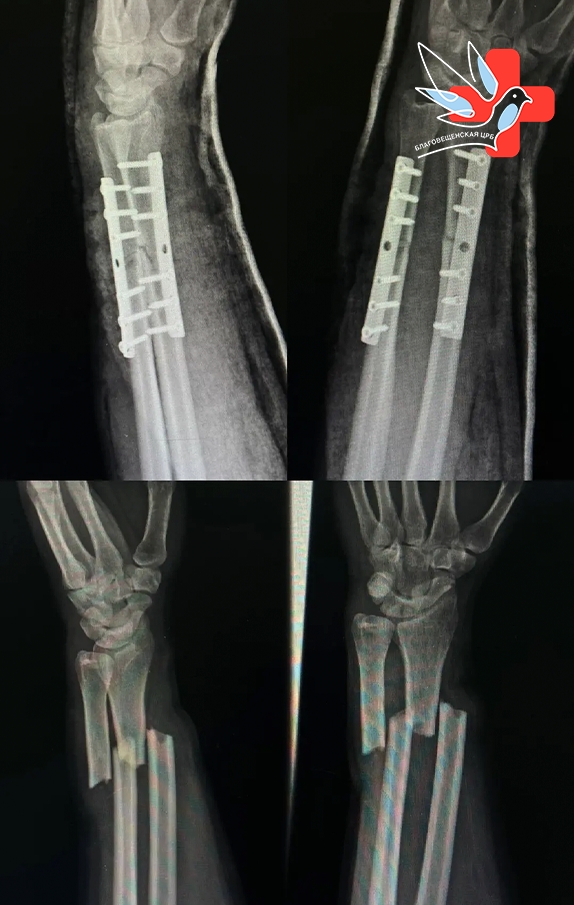

В травматологическое отделение Благовещенской ЦРБ поступил 50-летний мужчина с серьезной травмой. Поскользнувшись, он упал на руку и получил перелом обеих костей предплечья. Травма требовала оперативного вмешательства.

Операция была проведена уже на следующий день. Мы выполнили остеосинтез — надежно зафиксировали кости с помощью двух металлических пластин. На контрольных снимках видно, что костные отломки точно сопоставлены, что создает оптимальные условия для правильного срастания.

Сейчас пациент готовится к выписке домой. Впереди восстановительный период продолжительностью 2-3 месяца. Под наблюдением врачей перелом полностью срастется, и человек вернется к привычному образу жизни.